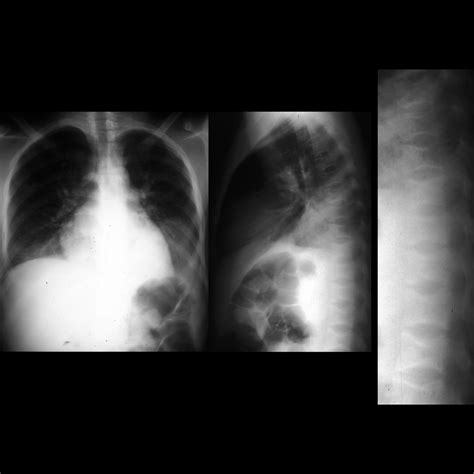

Acute Chest Syndrome is defined by the presence of a new pulmonary infiltrate on a chest X-ray, combined with clinical symptoms such as fever, cough, chest pain, sputum production, dyspnea, or hypoxia. While often triggered by a vaso-occlusive crisis or infection, the pathophysiology is multifactorial. In SCD, sickled red blood cells are rigid and misshapen, causing them to adhere to the endothelium and block blood flow, which leads to inflammation and injury within the lung tissue. This creates a feedback loop of worsening oxygen deficiency and further sickling, which necessitates immediate medical attention.

Once a patient is admitted, medical teams use a combination of diagnostics to confirm the diagnosis and assess severity. Standard procedures typically include pulse oximetry, chest radiography, and arterial blood gas analysis. Treatment is comprehensive and aggressive, focusing on reversing the sickling process and supporting respiratory function.